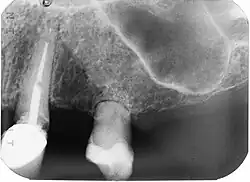

External Replacement Root Resorption

External replacement root resorption (ERRR) occurs due to replacement of the root surface with bone, i.e. ankylosis. ERRR can be further categorized as transient or progressive depending on the extent of periodontal ligament damage with the latter resulting in complete root resorption.[16]